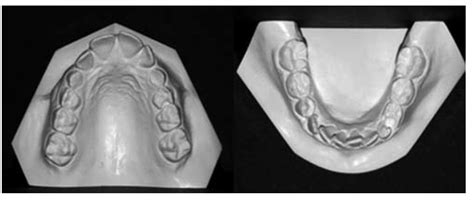

Figura 7A Vista oclusal de modelos pretratamiento.

Modelo superior Observamos una forma de arcada parabólica, con maxilar comprimido, incisivos superiores diastemados y mesiolinguorrotación de ambos primeros molares superiores (fig. 7A).

Figura 7B Modelos pretratamiento en máxima intercuspidación.

Modelo inferior La arcada describe una curva catenaria, con falta de espacio en la región de incisivos inferiores, que se encuentran apiñados. La discrepancia oseodentaria inferior, estimada en función del percentil 75 de las tablas de Moyers, es de -6,6 mm (fig. 7A).

Modelos en máxima intercuspidación Existe una relación molar de Clase II bilateral, siendo completa en el lado derecho e incompleta en el lado izquierdo. La línea media inferior se desvía 1,5 mm hacia la derecha con respecto a la línea media superior. El resalte está aumentado, siendo de +11 mm. Podemos calificar la sobremordida como completa o de 3/3 (fig. 7B).